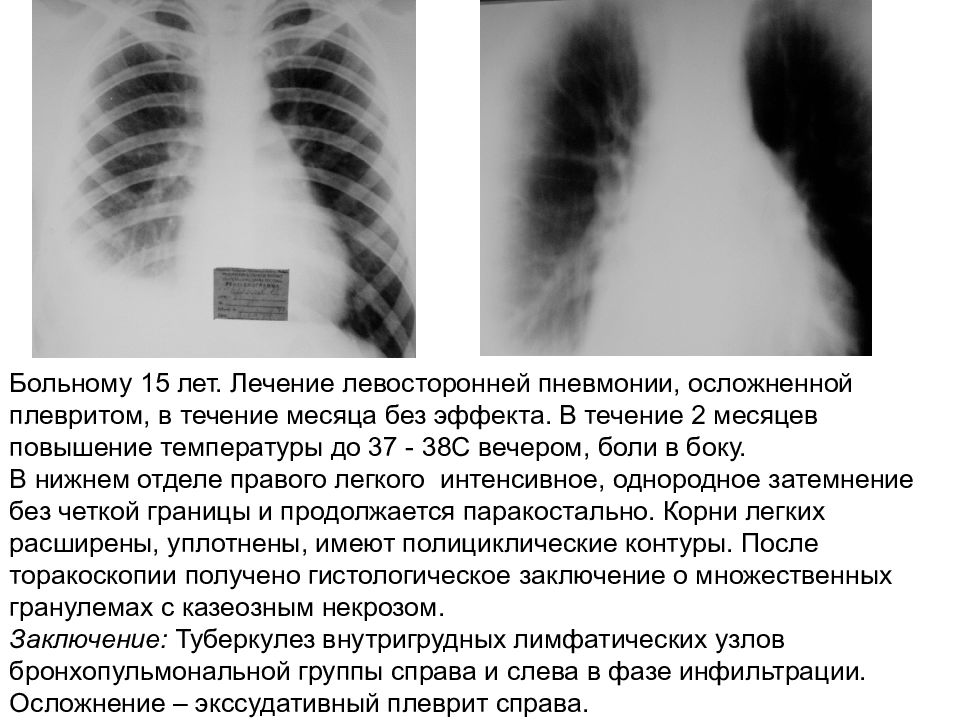

Медицинская тема: легочные осложнения при пневмонии